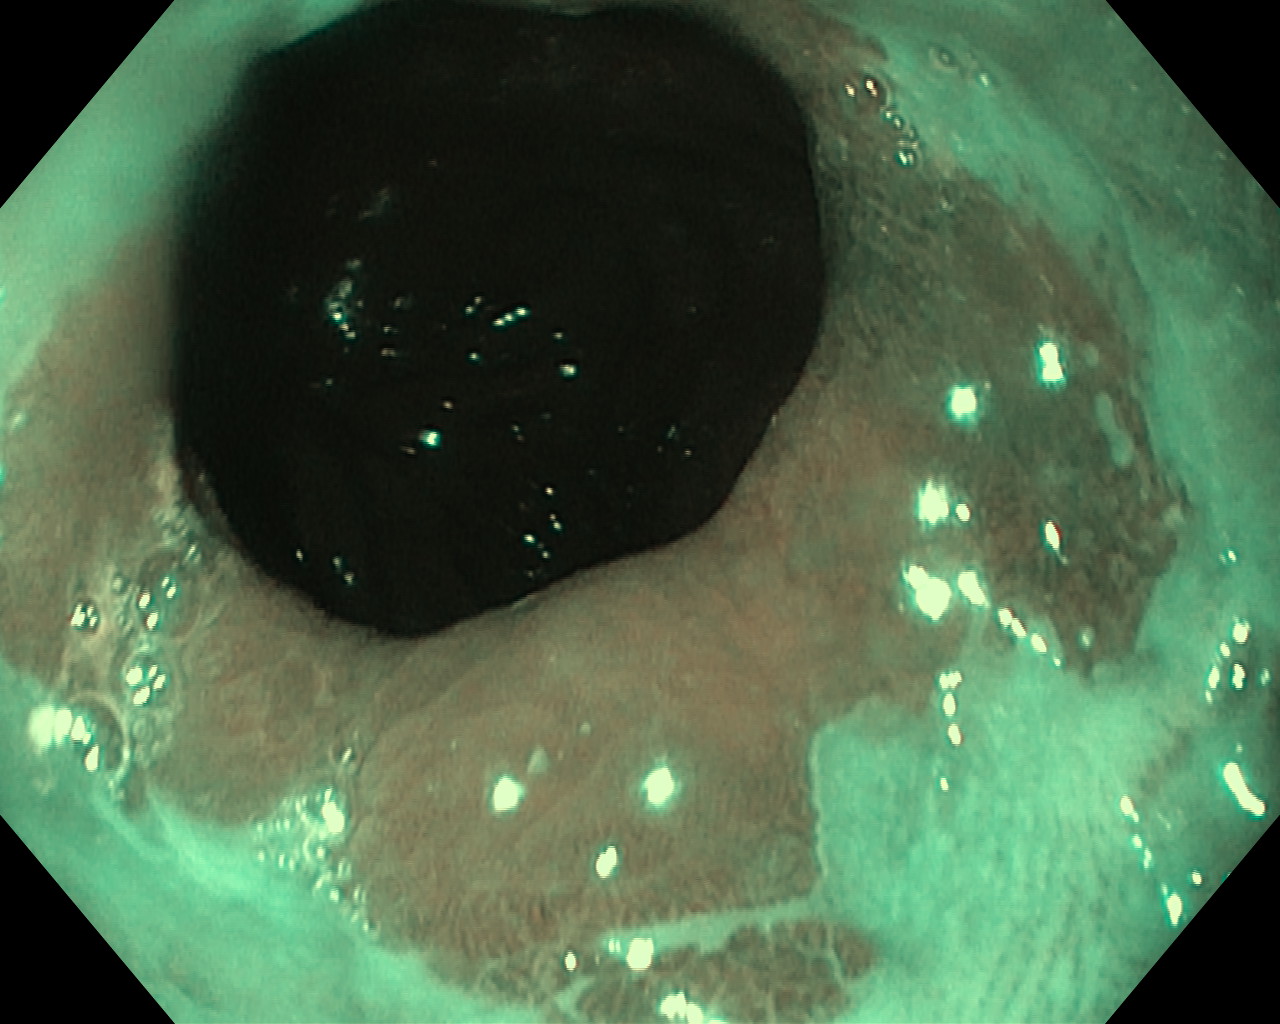

Przełyk Barretta